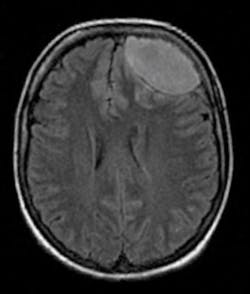

Figure 1: Oral-antral communication due to a post operative infection

Figure 2: Brain abscess due to the mismanagement of a post operative complication